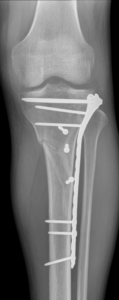

Nonunion and malunion repair related to post-traumatic conditions and/or prior surgery

Acute fracture care of the pelvis and the extremities